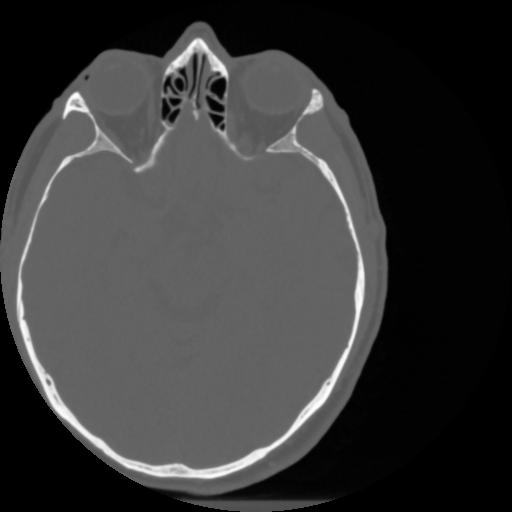

4 CEREBRO,,Vol,0.5,CEREBRO,,